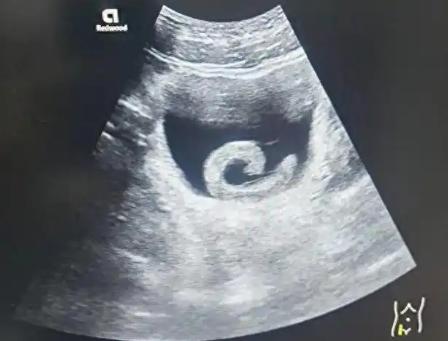

真是让人听了都觉得后背发凉! 1月6日,郑州某医院接诊了一个让人“叹为观止”的病例。一名23岁男子网购了5厘米长的活水蛭,竟然往自己尿道里塞。结果这水蛭也是个“狠角色”,不仅没被尿冲走,反而逆流而上,一路“长征”钻进了男子的膀胱。 进了膀胱后,这只水蛭依然生龙活虎,在这么娇嫩的器官里疯狂吸血。男子被折腾得疼痛难忍,实在扛不住了才去医院求救。医生费了好大劲才把这只“不速之客”请出来。 这操作咱就不评价了,单说这胆量,一般人真比不了。看着都头皮发麻的东西,他竟然敢往自己身上招呼,真是个狠人! 我看这小伙子也是太缺乏常识了。身体发肤受之父母,怎么能拿自己的健康开玩笑?这种为了猎奇或者所谓的“偏方”而不顾身体安危的行为,简直是拿生命在冒险。 有这股“狠劲”和胆量,要是能用在学习、工作或者正经事业上,遇到困难不退缩,那指定能干出一番成绩来。年轻人还是得把心思用在正道上,珍爱生命,别再整这些让人啼笑皆非的“幺蛾子”了。